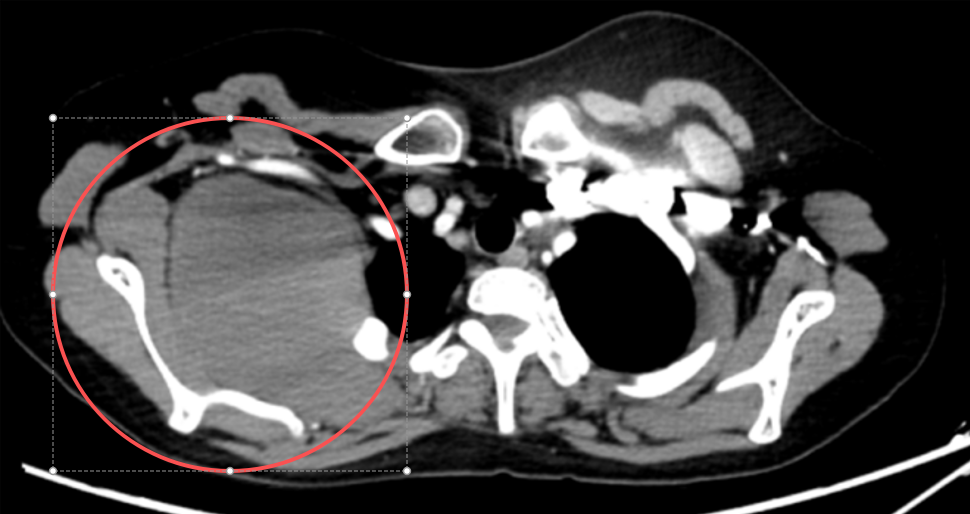

MRI及CT结果提示,肿瘤血供极其丰富,侵犯并包绕右侧第1-4肋骨,累及胸膜及部分肺组织,与锁骨下动静脉、臂丛神经、肩胛骨及右侧乳腺紧密相邻。

如此复杂的病情使手术面临多重风险:臂丛神经损伤,术后可能导致右上肢活动障碍;肿瘤血供丰富及锁骨下动静脉损伤,术中大出血严重时危及生命;大范围胸壁缺损重建,需进行复杂的胸壁及肋骨重建;创面修复和术后感染控制问题……